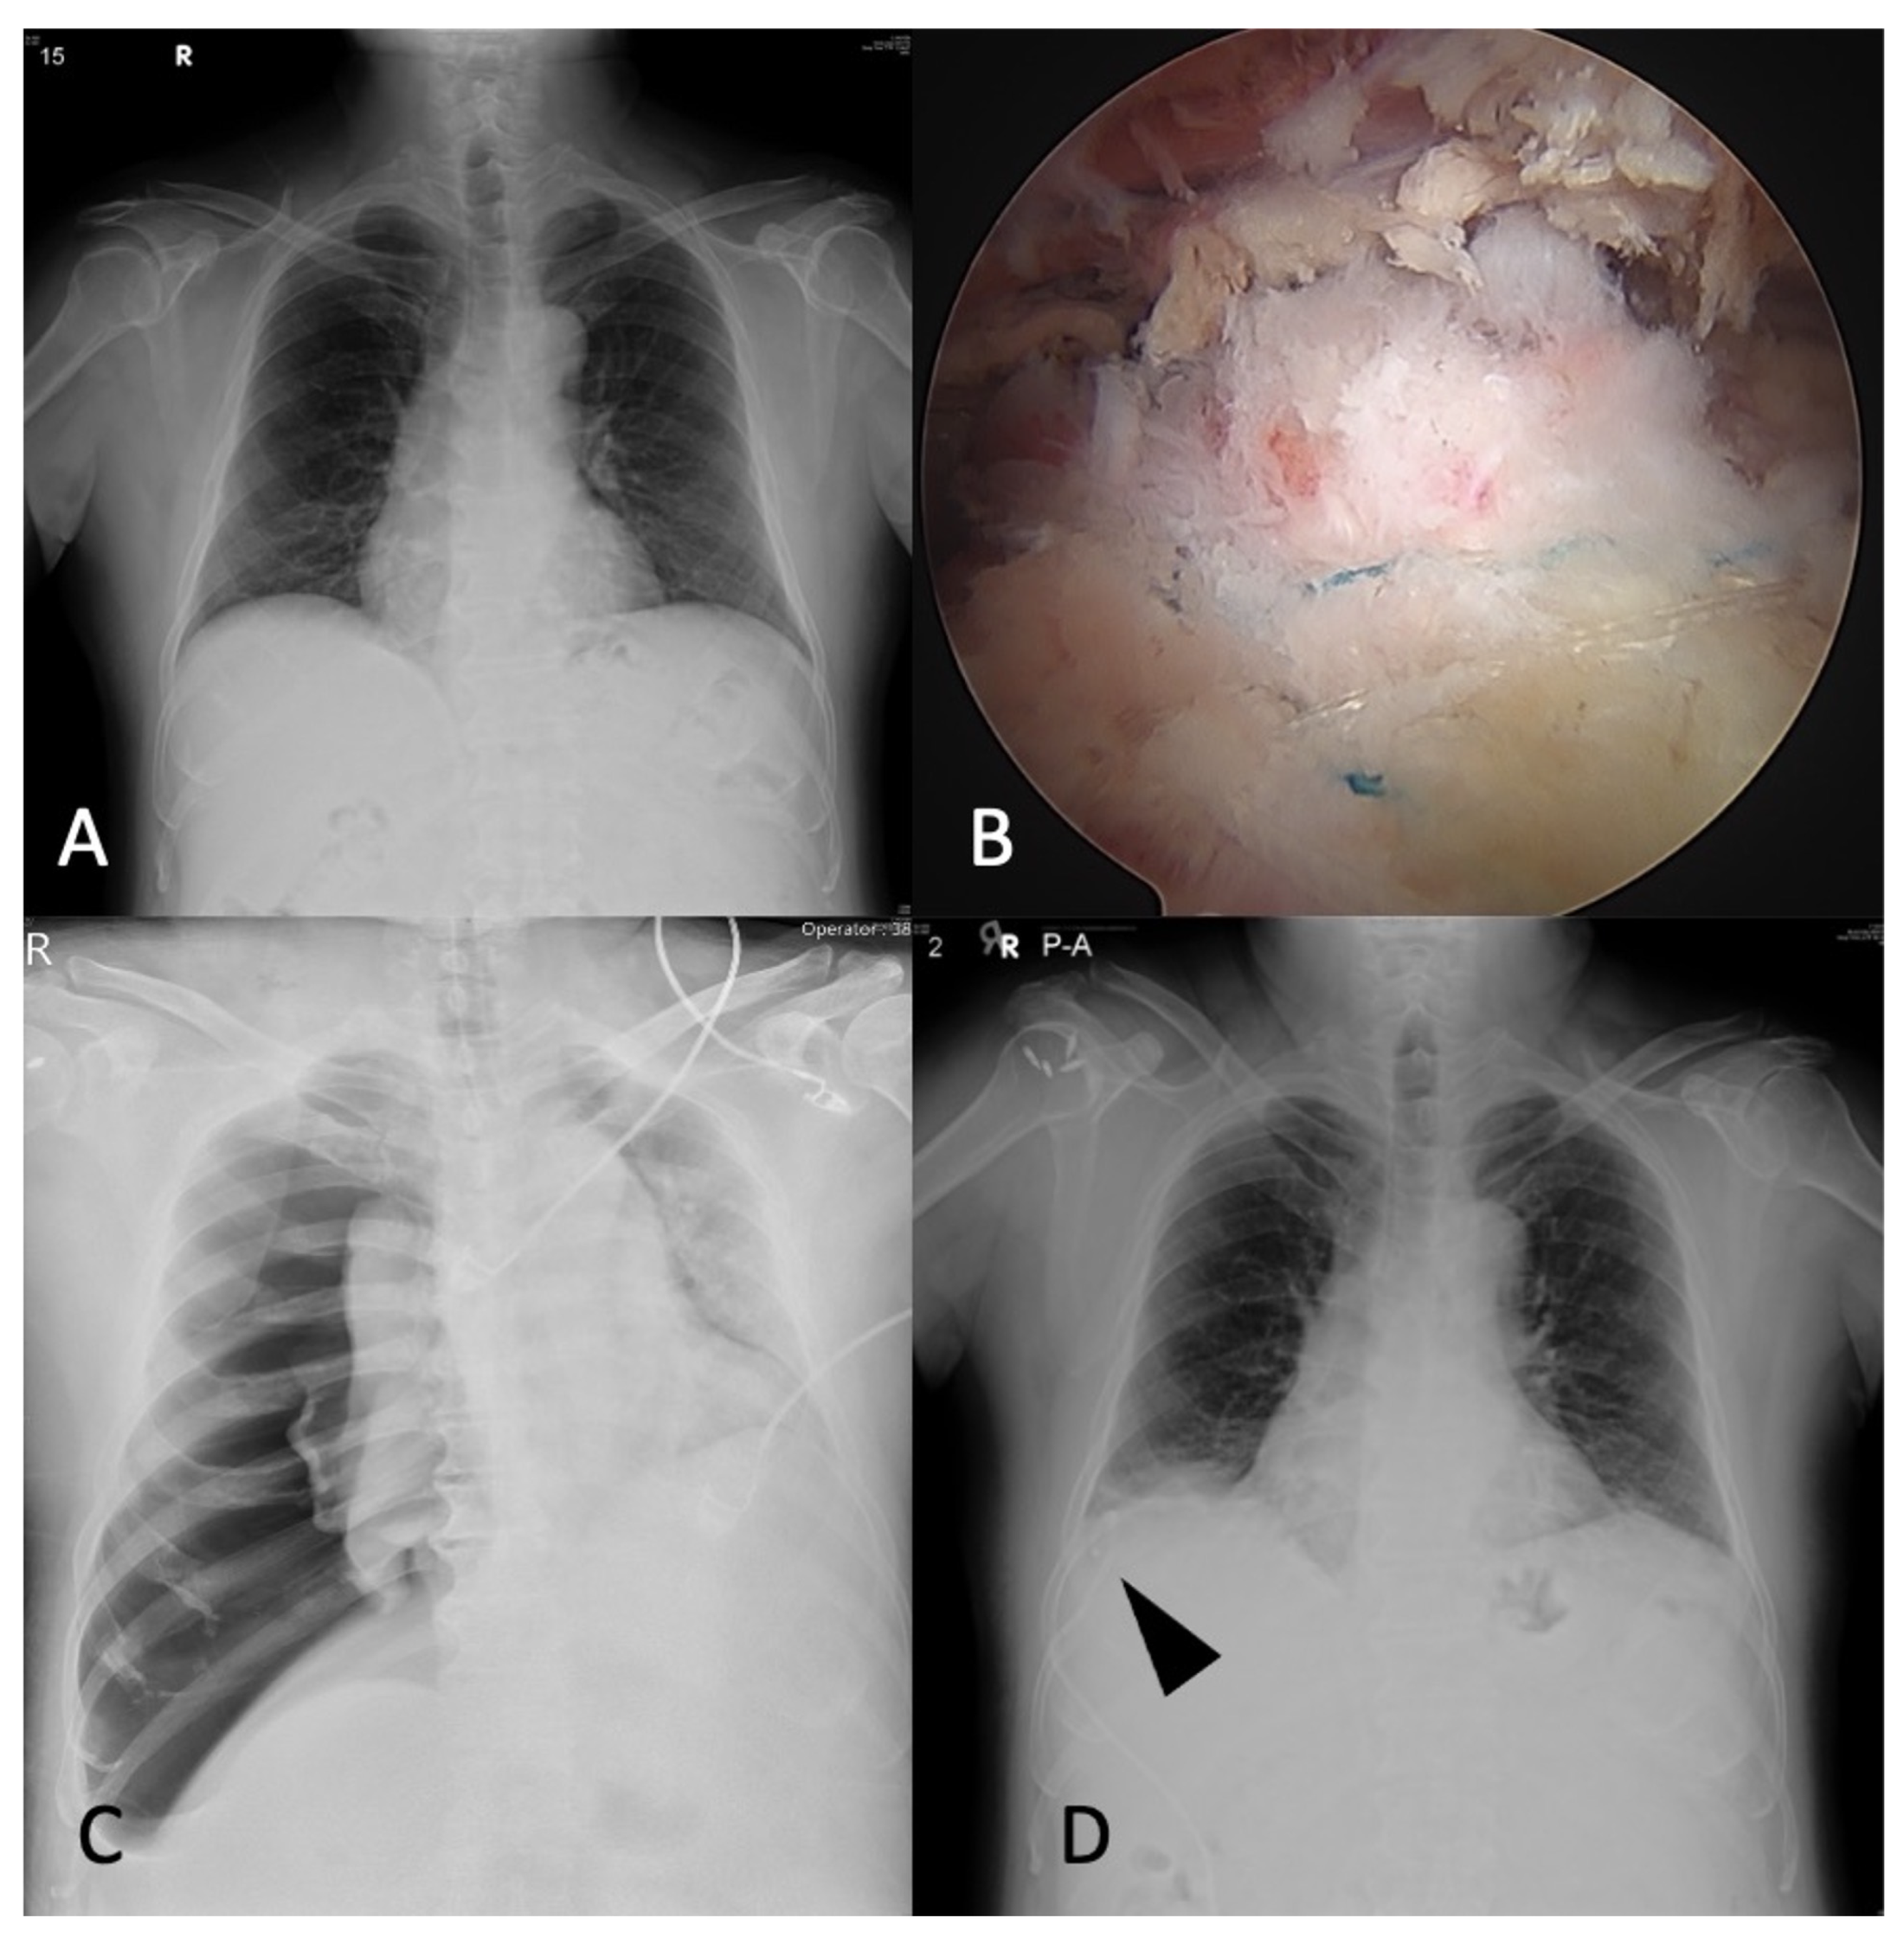

2. Clinical Cases

2.1. Case 1

2.2. Case 2